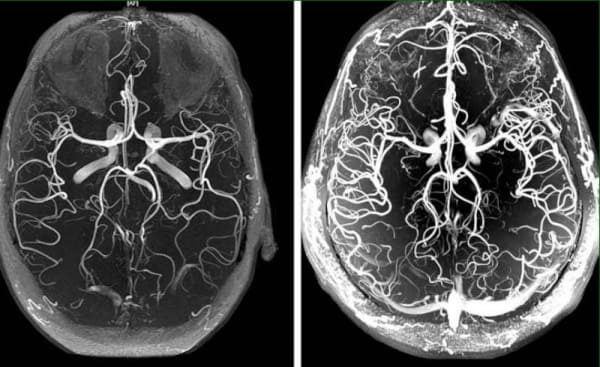

თავის ტვინის სისხლძარღვების ანგიოდისტონია წარმოადგენს ორგანიზმის სისხლძართვების ქოლესტერინით “დაბინძურების” - ათეროსკლეროზის - საწყის ნიშანს. თავის ტვინის სისხლძარღვები. თავის ტვინის სისხლძარღვებში სისხლის მომიქცევის მკურნალობის საფუძველს წარმოადგენს მთელი ორგანიზმის ძარღვების დაგროვებული დამაბინძურებული მასალისგან გაწმენდა. ესენია ქოლესტერინის ფირფიტები, თრომბები და კალციუმის გროვები.